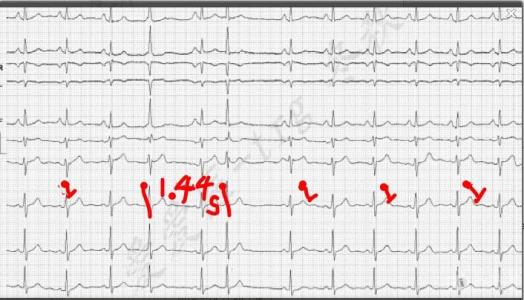

过早搏动简称早搏。是指异位起搏点发出的过早冲动引起的心脏搏动,为最常见的心律失常。可发生在窦性或异位性(如心房颤动)心律的基础上。可偶发或频发,可以不规则或规则地在每一个或每数个正常搏动后发生,形成二联律或联律性过早搏动。按起源部位可分为窦性、房性、房室交接处性和室性四种。其中以室性早搏最常见,其次是房性,结性较少见。窦性过早搏动罕见。早搏可见于正常人,或见于器质性心脏病患者,常见于冠心病、风湿性心脏病、高血压性心脏病、心肌病等。早搏亦可见于奎尼丁、普鲁卡因酰胺、洋地黄或锑剂中毒;血钾过低;心脏手术或心导管检查时对心脏的机械刺激等。

过早搏动可无症状,亦可有心悸或心跳暂停感。频发的过早搏动可致(因心排血量减少引起)乏力、头晕等症状,原有心脏病者可因此而诱发或加重心绞痛或心力衰竭。听诊可发现心律不规则,早搏后有较长的代偿间歇。早搏的第一心音多增强,第二心音多减弱或消失。早搏呈二或三联律时,可听到每两或三次心搏后有长间歇。早搏插入两次正规心搏间,可表现为三次心搏连续。脉搏触诊可发现间歇脉。